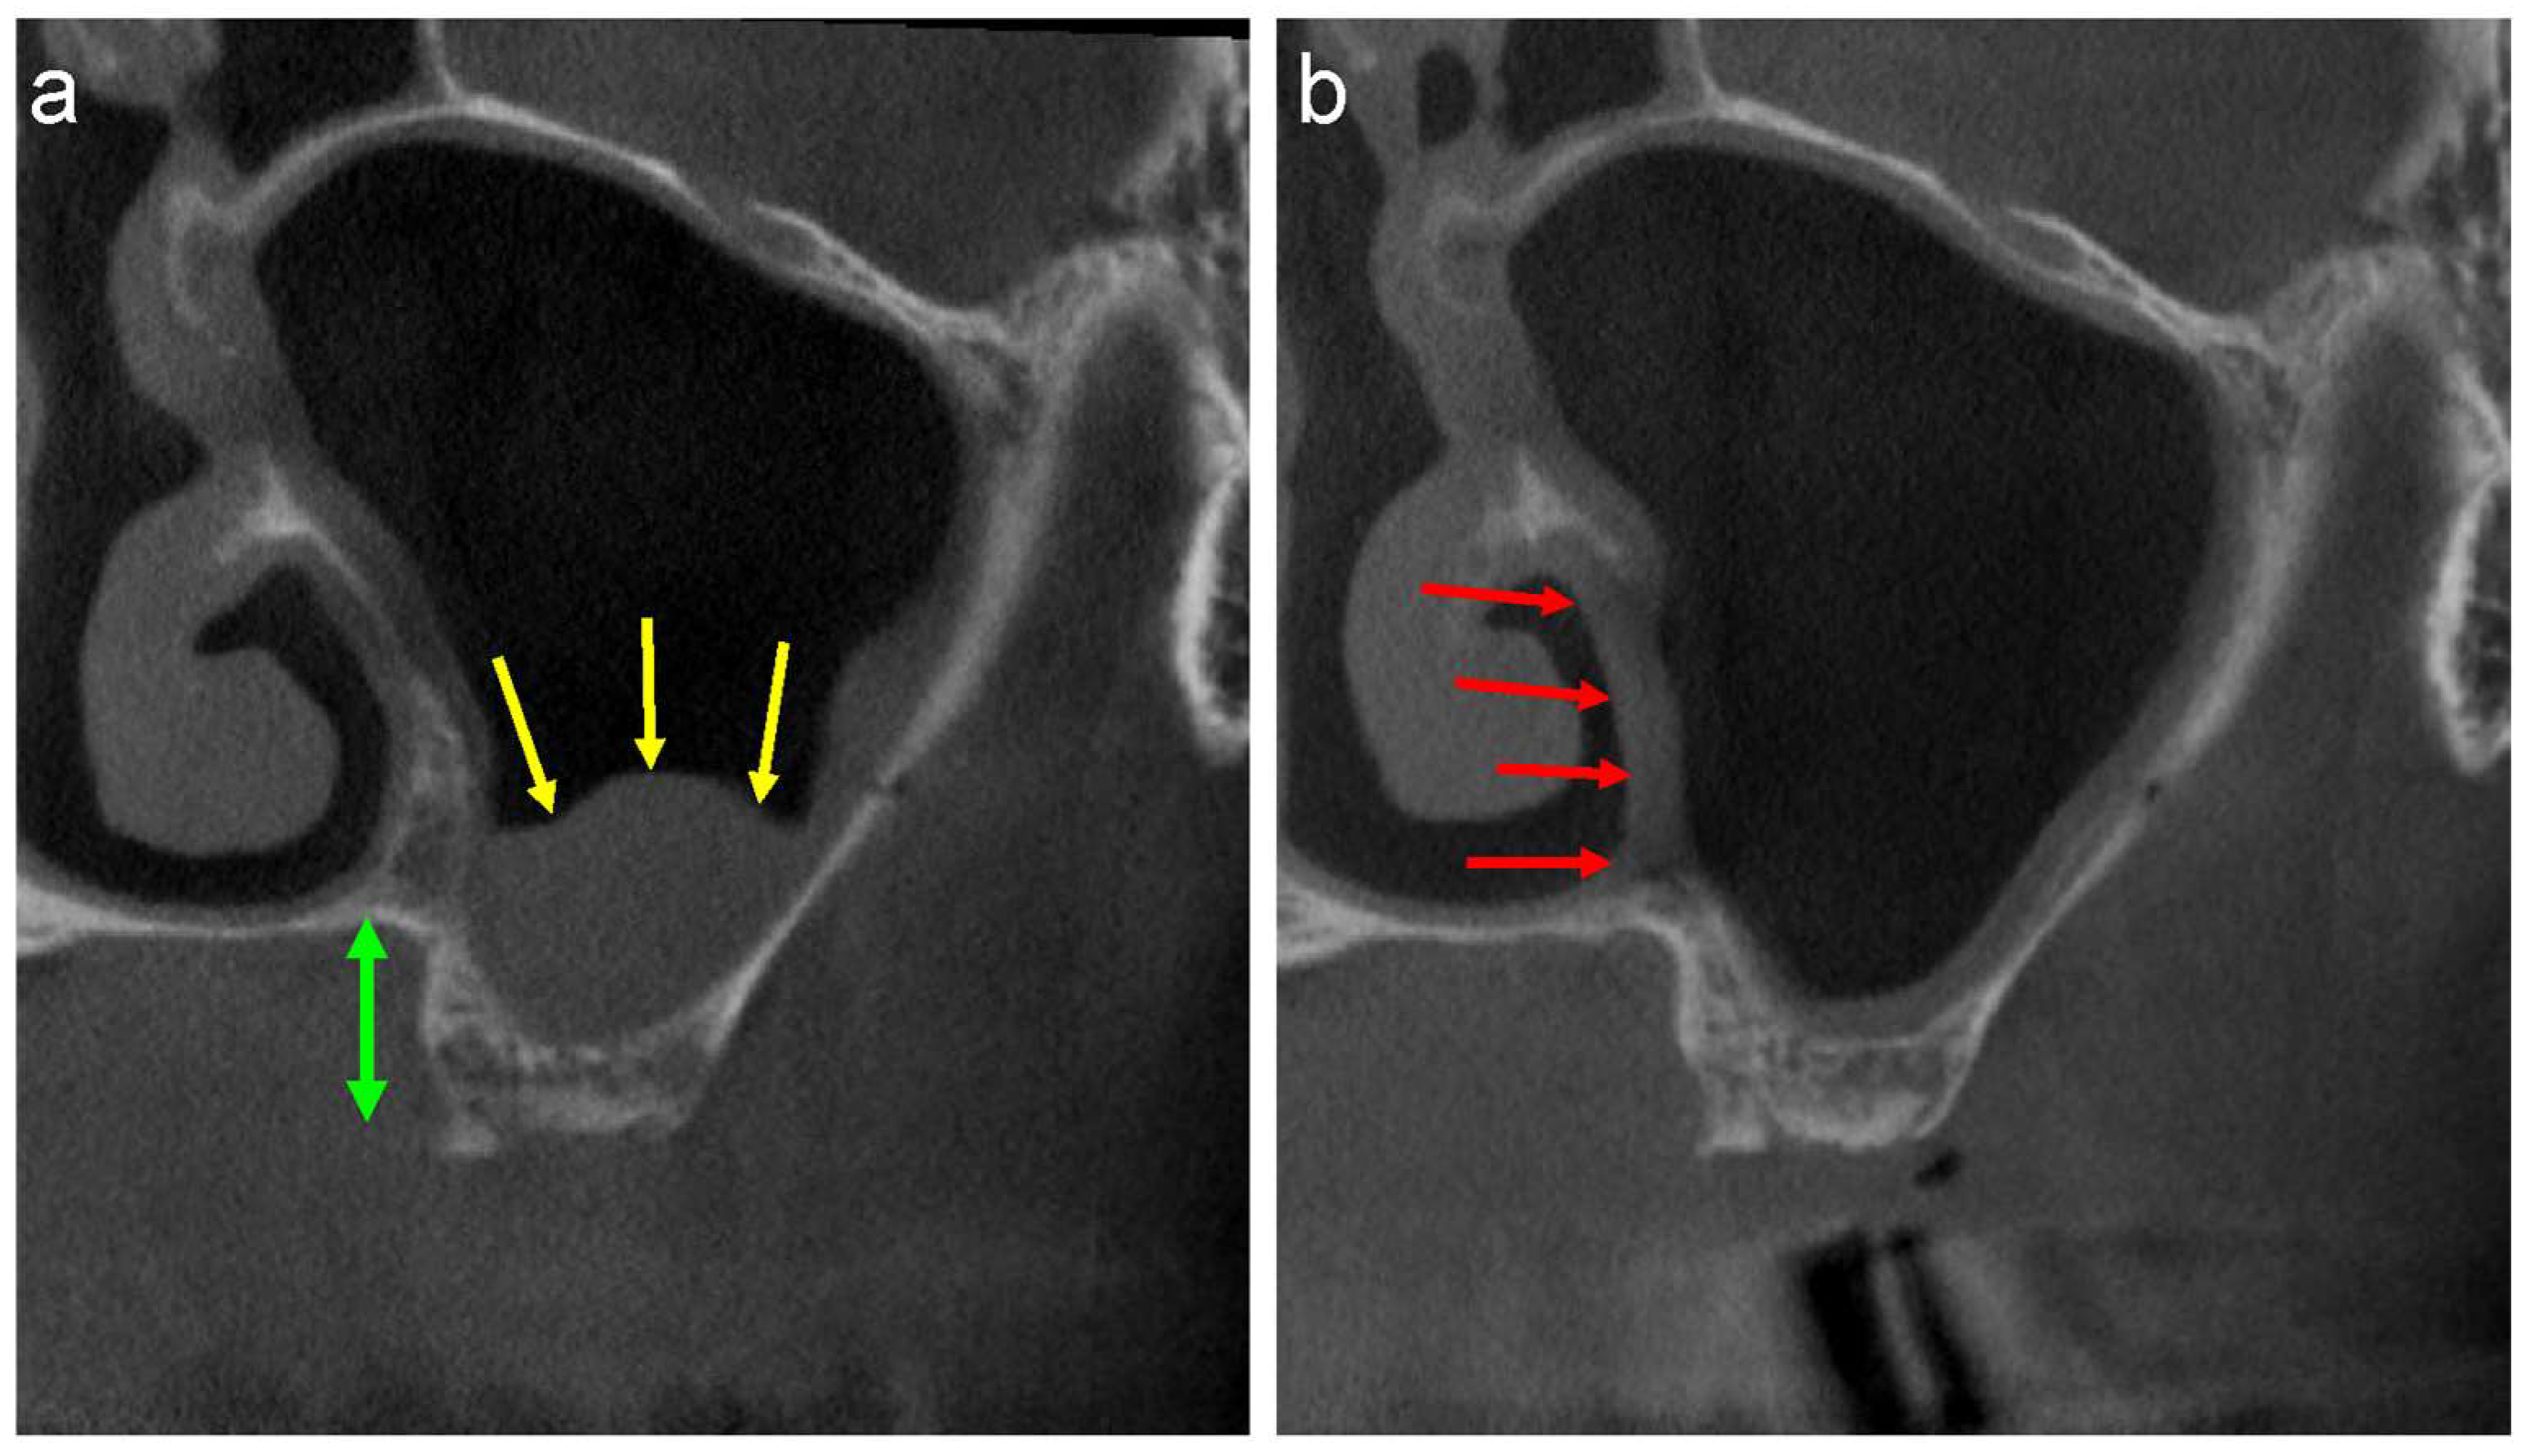

Endoscopic intranasal sinus surgery, a method commonly used to remove maxillary sinus cysts, is another surgical procedure commonly used for the enucleation of APs [20,21]. However, this surgery is usually performed by an ENT surgeon under general anaesthesia. The medial wall of the maxillary sinus must be removed when the surgeon approaches the inferior nasal meatus in this approach. Sinus floor elevation is difficult to perform in cases where the distance between the alveolar crest and the floor of the nasal cavity is short (Figure 6a, green arrows) owing to the bone defect in the medial wall (Figure 6b, red arrows). Therefore, a preoperative discussion between the ENT and oral surgeons is necessary.

Figure 6.

(a) The buccolingual section of the CT image shows well-defined, faintly radiopaque antral lesions (yellow arrows), and the distance between the alveolar crest and bottom of the nasal cavity is short (green up-down arrow). (b) A bone defect in the medial wall is observed following the removal of the lesion by the ENT surgeon (red arrows).